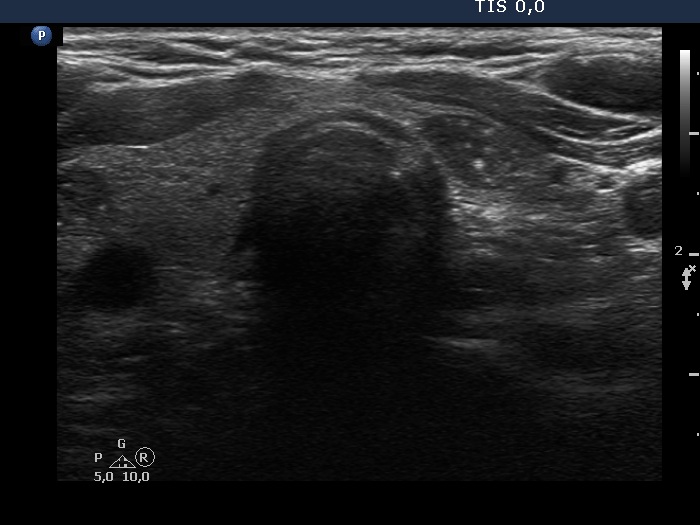

Left lobe, transverse scan. This nodule is also hypoechoic.